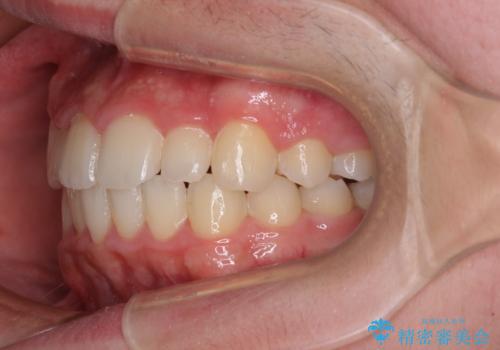

中学生のワイヤー矯正 クロスバイトを短期間で改善

- 前歯のクロスバイトを気にして来院された患者様です。

中学生であることから、治療期間を短縮できると判断し、ワイヤー矯正にて短期間で治療を行うこととしました。

叢生のため磨き残しの多い歯列でしたが、1年弱で治療を終了でき、磨き残しや歯肉の腫れが著しく改善されました。